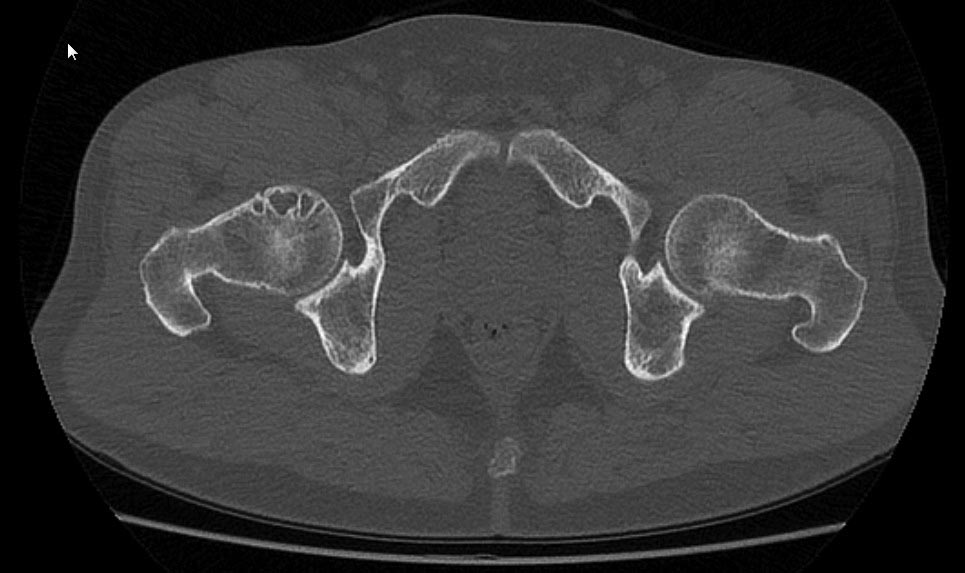

Спортсмен (тайский бокс), тренер, 42 года, пожаловался на боли в

ягодичной области, возникающие при подъеме и переносе тяжестей. При

тренеровках в полную нагрузку болей нет.

Тесты на iliopsoas, наружные ротаторы отрицательны. Есть небольшая

болезненность при пальпации в области седалищного бугра. На МСКТ

выявлена кистозная перестройка головки правого бедра. Скажите, коллеги,

есть ли у пациента альтернативный эндопротезированию вариант. Очень

хочется сохранить в нашем городе хорошего тренера для молодого поколения.